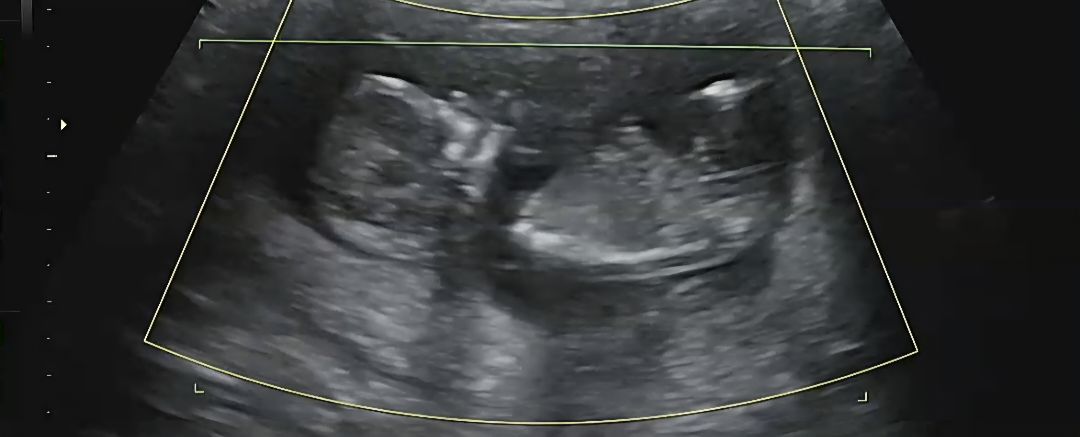

각도법 잘보시는분 도와주세요!

혹시 알수있을까요??ㅎㅎㅎㅎ

가운데 튀어나온거로 봐선 아들같아요 ㅋㅋㅋ

어멋 아들일까요??!! 감사합니다!!